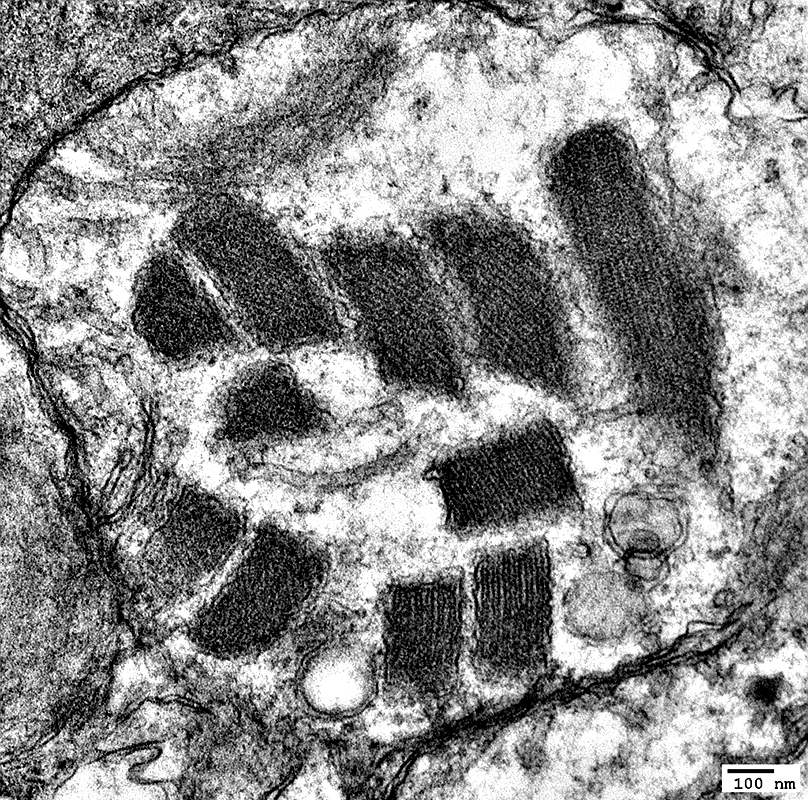

MNGIE: Muscle Ultrastructure

From: R Schmidt